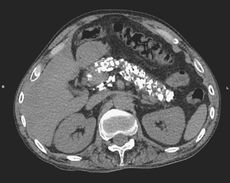

Stone Cold Vodka? Drinking Habit 'Calcifies' Man's Pancreas

A 50-year-old man who drank half a pint of vodka a day for more than a decade developed numerous calcium deposits in his pancreas.